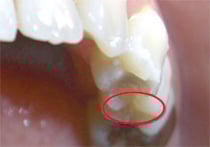

外観からはほとんどむし歯を見つけることができません。

全く症状のない大きなむし歯がレントゲンにて観察されます